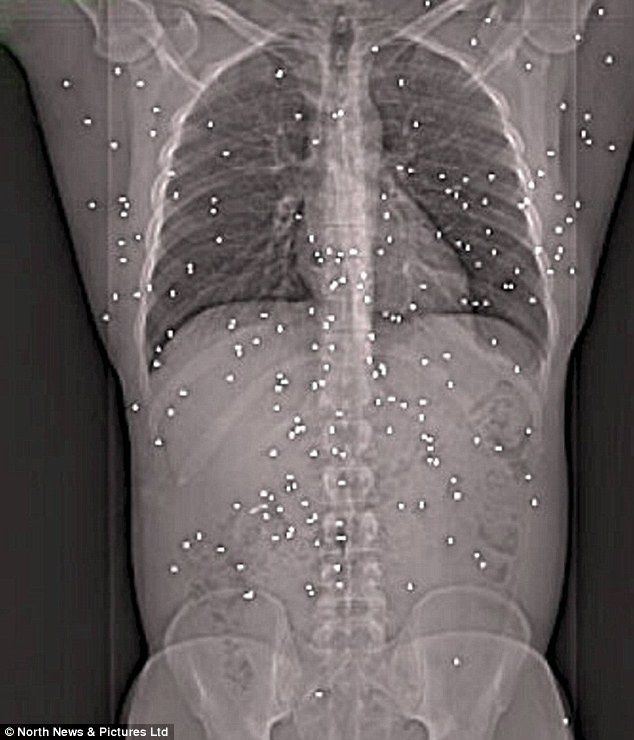

A close-range shotgun blast to the torso (see picture) can incapacitate an attacker and end the confrontation faster compared to other weapons. The shotgun's ability to fire multiple times with each trigger pull gives it a unique advantage in home self-defense.